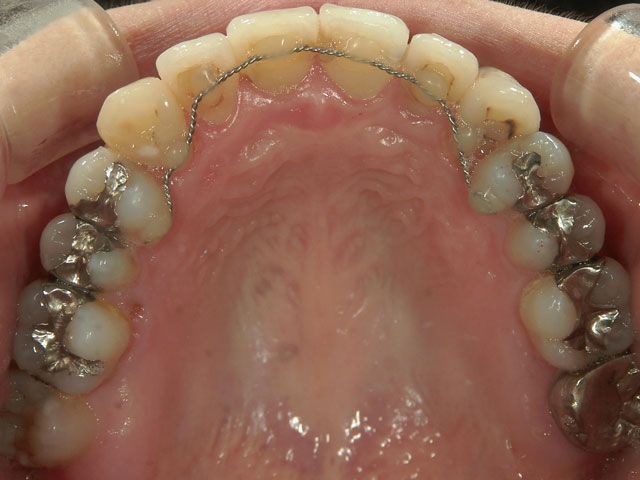

矯正歯科 治療前矯正歯科 治療前

28歳女性 浜松市中区在住

治療期間2年6ヶ月

矯正歯科 治療前 外科手術併用(コルチコトミー)、非抜歯